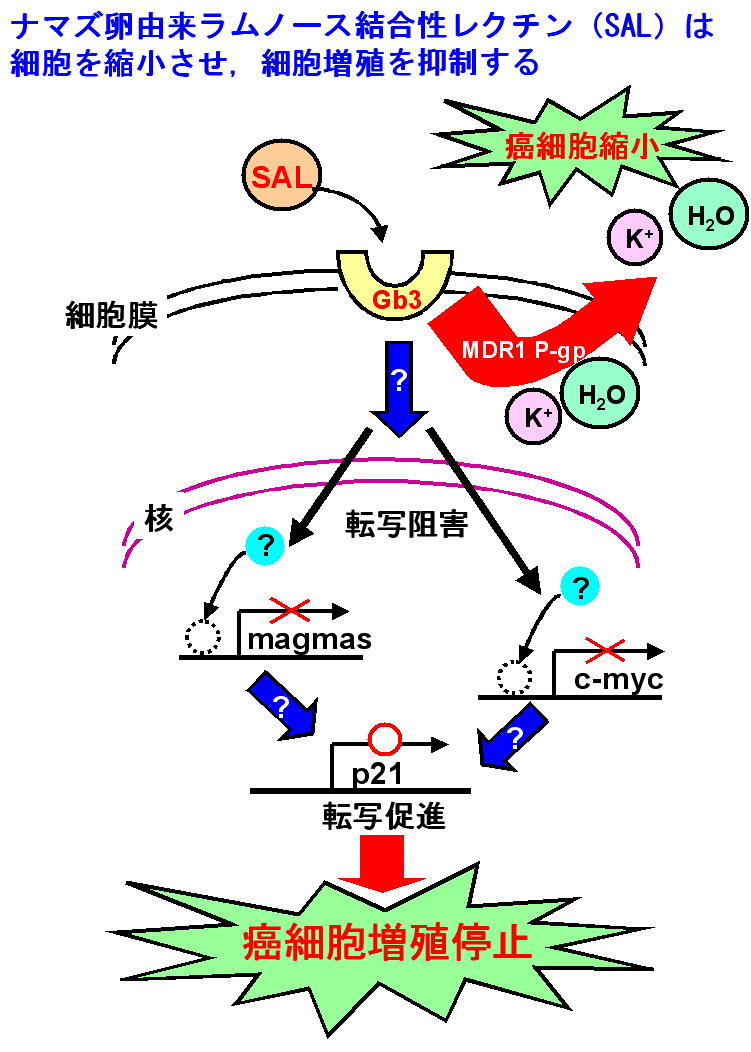

ナマズなどの魚卵には,ラムノース結合性レクチン(RBL)が含まれている.ナマズ卵由来RBL(SAL)は285アミノ酸から成り,95残基ずつの互いに相同性の高い3つのドメインから成る繰り返し配列を有するタンパク質で,バーキットリンパ腫細胞(RajiやDaudi)の糖脂質グロボトリアオシルセラミド(Gb3)に選択的に結合し,この細胞を短時間で縮小させる.しかし,細胞死は誘導しないユニークな性質を持っている.また,SALはこれらの細胞の細胞周期を停止させ,細胞増殖を阻害する働きもある.SALを利用して糖脂質糖鎖の情報伝達機構を明らかにできる可能性がある.

現在,想定されている機構を下記の図に示す.